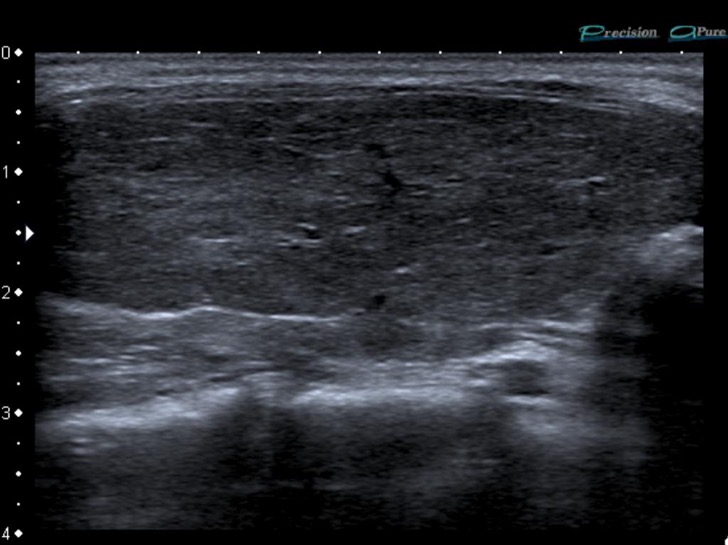

IMAGERIE

US (très douloureuse): hétérogène avec plages hypo-échogènes en flaque d’huile peu vascularisées